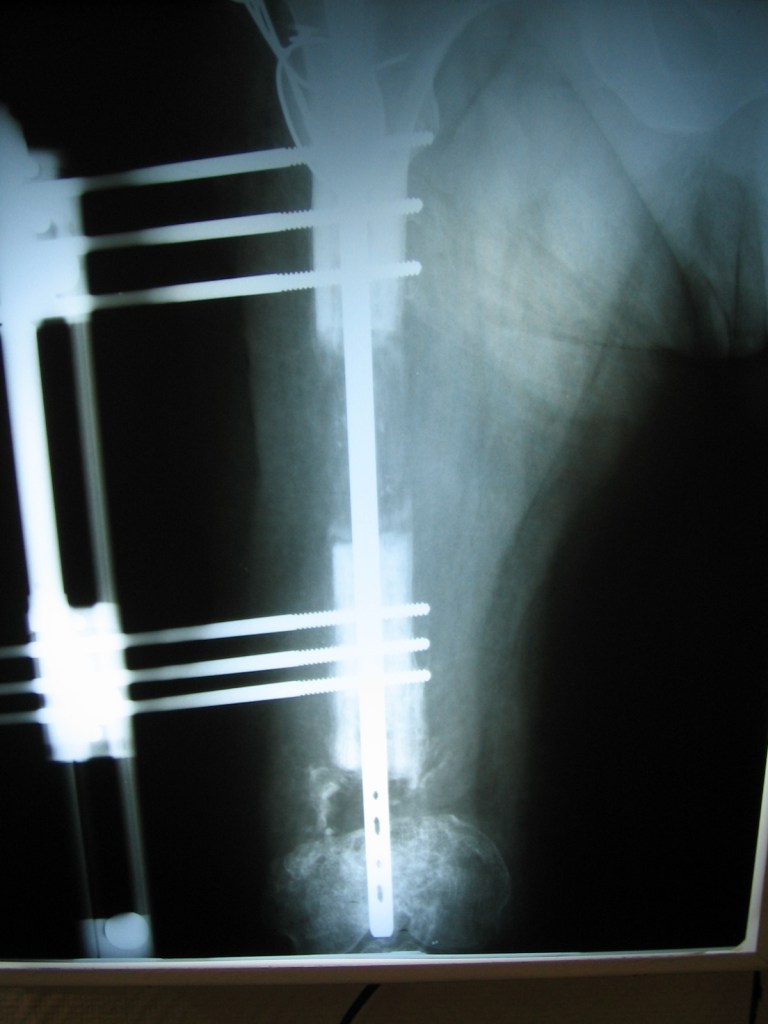

niño de 6 años con osmelitis en tibia

Luego de una fractura , mi hijo a los 6 años adquirió una infección ósea con exposición del hueso , que no podía tratarse en Chaco, por lo que tras una consulta con el Dr Dratewka , se explico las opciones de tratamiento

Luego de una 1 cirugía que consistió en remover todo el tejido muerto y acortar el hueso , pudimos tratar la infección ,y en una 2 cirugía alargar la pierna nuevamente

Hoy mi hijo ha podido volver a todas sus actividades